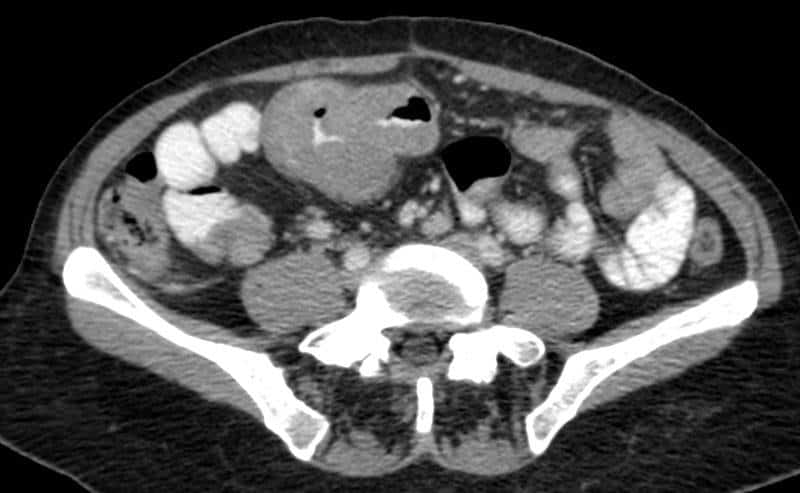

Di căn ruột non - Ảnh 4

Di căn ruột non

» Thông tin: Nữ giới – 56 tuổi.

» Lâm sàng: Đau bụng.